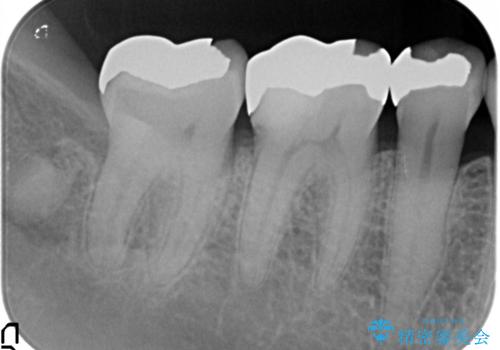

- 口を開けると銀歯が見えるのが嫌とのことで来院。

銀歯を外し、拡大鏡下で虫歯を全て取り除き、白い詰め物(e-maxインレー)にて治療することになりました。

まずは一つ治療したいとの事だったので手前の小臼歯から行いました。

- e-maxインレー 7.7万円 費用は治療当時の料金となります